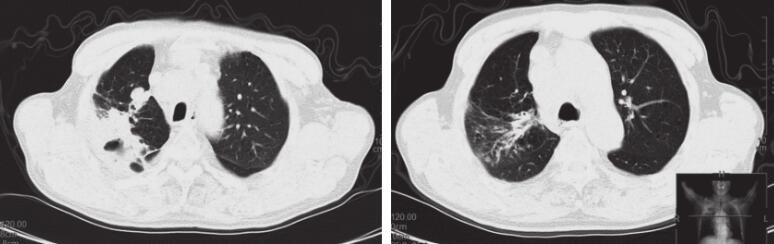

入院后先后给予“亚胺培南西司他汀、左氧氟沙星+万古霉素”抗感染等综合治疗,上述症状无缓解,复查胸部CT示病灶较前增多(图1),遂于2014年11月24日行CT引导下经皮肺穿刺活检术,病理示“机化性肺炎”,调整抗生素为“头孢哌酮舒巴坦”,同时给予“甲泼尼龙”应用后症状逐渐好转,后复查胸部CT示病灶较前明显吸收,但右上肺结节及纵隔多发淋巴结无明显变化。复查癌胚抗原42.96ng/ml,考虑恶性肿瘤可能,于2014年12月10日行TBNA检查,病理提示找见恶性肿瘤细胞,倾向小细胞癌。患者及家属要求出院,告知相关风险,表示理解,后患者再次出现反复发热,最高38.5℃,热型不规则,发热前无寒战,复查胸部CT示右肺结节样病灶较前略增大,提示肺癌在进展。于2014年12月27日行“EP”方案化疗,具体剂量:依托泊苷0.1g d1~3,顺铂30mg d1~3,并继续给予甲泼尼龙片口服,并逐渐减量。患者体温逐渐降至正常,咳嗽、咳痰症状逐渐好转,咯血、胸痛症状消失。

图1 2014年11月15日(A)、2014年12月25日(B)、2015年1月14日(C)CT表现

右肺可见斑片状高密度影,右上肺见结节影。经治疗后右上肺斑片影较前明显吸收,右上肺结节较前增大后又趋于稳定。现仍处于随访中